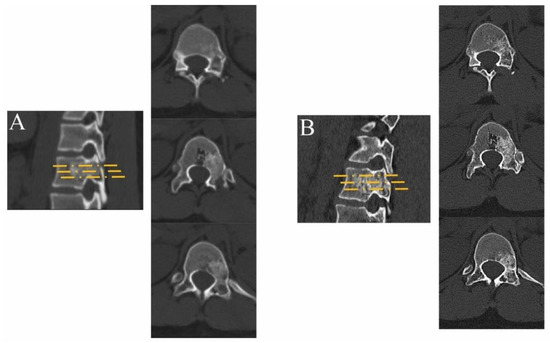

2. Materials and Methods

2.1. Preoperative Preparations

2.2. Surgical Technique

3. Results